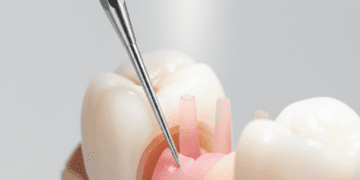

O exame clínico permite avaliar visualmente o desgaste e a presença de alterações na superfície dentária. Manifestações típicas de erosão incluem o desgaste em áreas expostas a ácido, como faces palatinas dos dentes superiores em casos de refluxo.

Para casos iniciais, o controle dos fatores de risco e a aplicação tópica de flúor, sob a forma de vernizes ou uso diário de cremes dentais fluorados, são eficazes para remineralizar as áreas comprometidas.

Nos casos mais avançados, a odontologia restauradora oferece opções como resinas compostas, facetas, coroas e outras restaurações que protegem o dente, recuperando forma e função. A escolha do material e técnica depende da extensão da erosão, da localização dos dentes afetados, da estética e da função mastigatória.